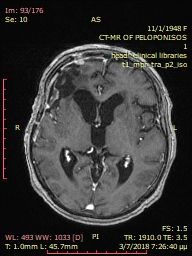

Pre-operative brain meningioma

Preoperative large brain meningioma.

Pre-operative ectopic cerebral meningioma.